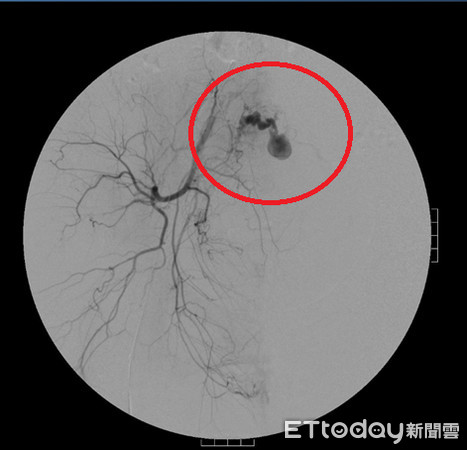

▲子宮右側血管瘤是造成延遲性大出血主因。(圖/國泰醫院提供)

目前產後出血的處置方法視引起產後出血的原因而定,臨床上先以藥物治療,若藥物治療無效時則採手術處理,方式包括B-Lynch縫合術、子宮切除術或經導管動脈栓塞術。經導管動脈栓塞術是利用血管X光攝影方式,將微導管沿股動脈尋找至出血點,再以一種栓塞物打入動脈內或以氣球將供應子宮血液的動脈塞住,幫助產婦止血,子宮也得以保留,此項手術方式不僅可降低失血過多的狀況,還能保留生育能力,對產婦而言可說是一大福音。